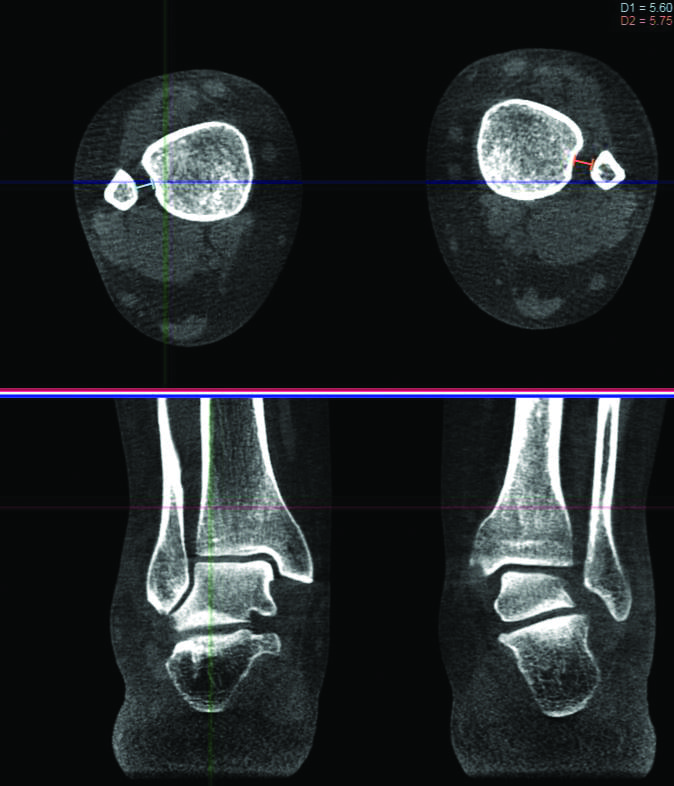

Until recently, all measurements of this motion had been conducted on cadavers or through non-weight bearing scans. In contrast, this study used a weight-bearing CT (WBCT) system to survey the ankles of 32 subjects as they stood on one foot, then the other.

They found a “total movement of 1.5 mm and rotation of 3 degrees” in the syndesmosis as the average across subjects. However, the study also found that intersubject variation was extremely high, meaning different people had vastly different ranges of motion despite similar orthopaedic histories.

These differences were not correlated with sex or age. Intrasubject variation, or the difference in movement between a person’s right and left foot, was significantly smaller and more consistent, less than 1 mm on average.

The study therefore concluded “the contralateral ankle should be used as a reference when dynamic alignment of the distal tibiofibular joint is studied.”